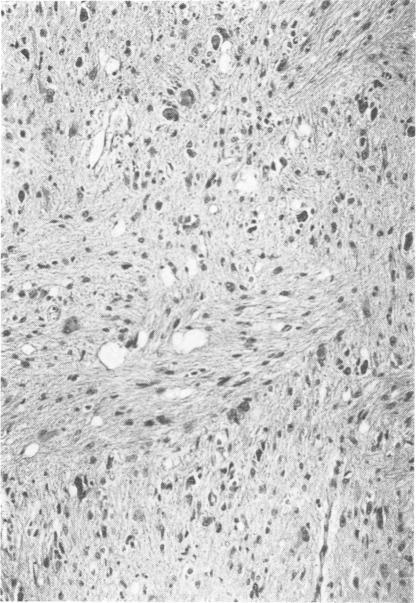

Thirteen cases of malignant glial tumours of the brain-stem that came to necropsy have been analysed in detail. These patients followed a rather uniform course defined by the early onset of signs and symptoms of increased intracranial pressure, poor response to radiotherapy, and short total duration of illness. Pathological features were also similar in all cases, with each tumour showing areas ranging from benign to frankly malignant. This regional variability points to the limited usefulness of small biopsies and also indicates the need for complete necropsy studies. The term `spongioblastoma polare' should probably be avoided, and it is suggested that the histological classification of glial brain-stem tumours be similar to the classification of such tumours elsewhere in the neuraxis.

对13例脑干恶性胶质瘤尸检病例进行了详细分析。这些患者病程较为一致,表现为颅内压升高的症状和体征出现早、对放疗反应差、总病程短。所有病例的病理特征也相似,每个肿瘤都有从良性到明显恶性的区域。这种区域变异性表明小活检的作用有限,也表明需要进行完整的尸检研究。“极性成胶质细胞瘤”这个术语可能应避免使用,建议脑干胶质瘤的组织学分类应与神经轴其他部位此类肿瘤的分类相似。